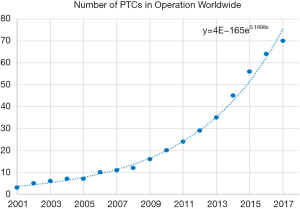

Proton therapy has been introduced to the world of radiation therapy since the 1950s (13). However, due to limitations of accelerator and magnet technology, traditional proton therapy machines were large, measuring several metres in width and height, and weighing hundreds of tons (14). Proton therapy is not widely used only until the early 2000s. A proton therapy machine has also become more affordable with the maturation of the technology, leading to an increase in Proton Therapy machine being constructed in hospital. Between 2010 and 2017, 50 new proton therapy facilities were started (15) (Figure 1).